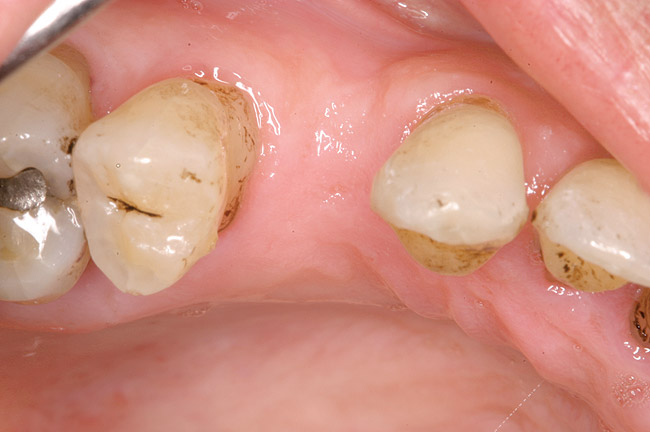

Figure 5  Recurrent decay of teeth Nos. 11 and 12. Note the proximity of the decay on both teeth to the osseous crest.

Figure 5

In treatment planning, the decay rate of the patient’s teeth, including the endodontic status of the individual tooth, becomes an important factor when considering long-term outcomes. In the pictured case (Figure 5), tooth No. 11, which previously had been treated endodontically, had recurrent decay and tooth No. 12 had advanced decay with endodontic involvement. In less than 30 days, recurrent decay that reaches the endodontic fill through a leaky restoration (temporary or not), ill-fitting crowns, or broken fillings can re-infect the entire length of the root canal system in a previously endodontically treated tooth.22 Therefore, saving a previously endodontically treated tooth, as in this case, may involve endodontic re-treatment, which can be a deciding factor for tooth preservation.

In addition, xerostomia becomes more likely with advanced patient age and/or the use of certain medications.23 This problem can lead to a higher decay rate, which has implications for a situation similar to the above case. In this case, in which tooth No. 12 would need endodontic treatment, surgical crown lengthening, a post, a crown, etc, to save it, the alternative of extraction and implant placement should be considered. The implant would not be susceptible to future decay, root fracture, or endodontic failure. The fee for this treatment also may be comparable to tooth preservation. If the tooth also requires a post, core, or other treatment, then its prognosis24 would be less optimistic than that of a dental implant. Also, if the implant can be placed at the time of extraction, there would be only one surgical visit; whereas, the endodontic and crown-lengthening procedures usually involve many treatment visits.

Bone removal is also a factor. In this example, tooth No. 12 had a short root. Removal of bone to reestablish a 3-mm biologic width as well as about 2 mm of ferrule25 would decrease the long-term prognosis of the tooth, especially because there would be an existing compromise regarding the crown-to-root ratio.26 Osseous recontouring for crown lengthening also may remove bone from the adjacent teeth (in this example, the distal of tooth No. 11).